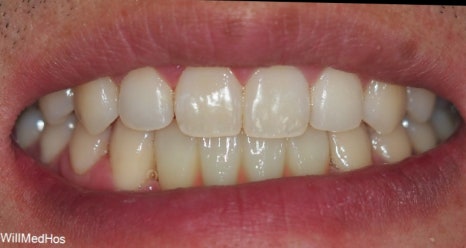

▲ FGG 완료 후 구강 사진

위의 사진은 잇몸 이식이 완료된 후 회복된 상태입니다

색상의 차이는 다른 부분의 조직이기 때문입니다!